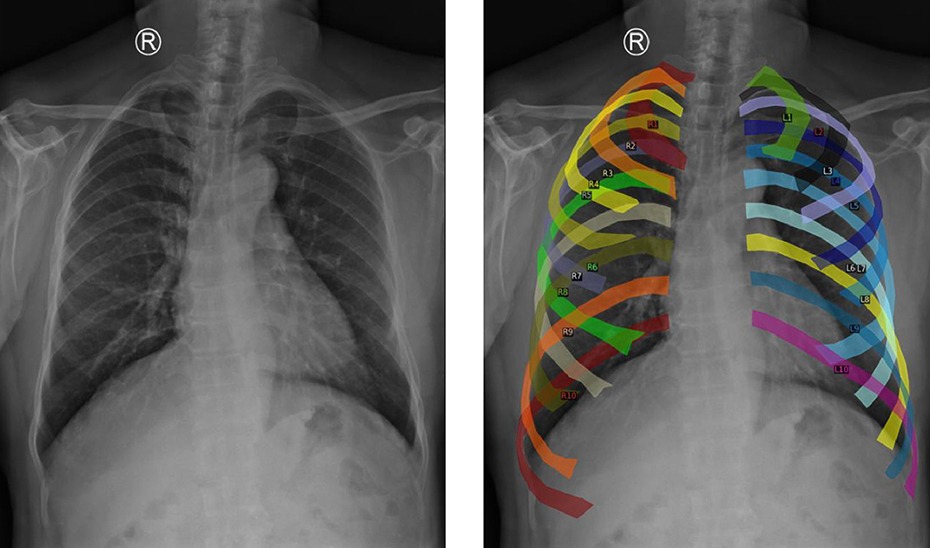

Para entrenar el modelo se utilizaron miles de radiografías de distintos hospitales, con una estrategia de aumento de datos que segmenta costillas y alinea puntos clave del tórax para crear imágenes homogéneas anatómicamente. Esto le permite mantener la precisión incluso ante pruebas de distintas resoluciones y equipos médicos.